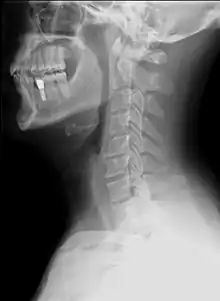

Examens paracliniques

Les examens dépendent du contexte et dans un premier temps seront simples

- Une radiographie du rachis cervical de face et de profil et en fonction de la localisation un autre cliché cette fois de face et la bouche ouverte pour voir les deux premières vertèbres cervicales ;